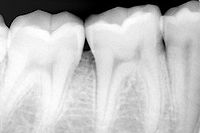

牙齿的X线片简称为“牙片”,也称口内标准片。其面积为3×4平方厘米。一张牙片可以显示3-4个牙齿。牙齿在牙片上显示出白色阻射影像。其中牙釉质阻射最强,牙本质牙骨质阻射低于牙釉质。牙髓腔呈黑色透明影像,根管口根尖孔呈逐渐变细的影像。

临床上,利用牙片对牙齿硬组织病变、牙髓病变、尖周病变及牙周病进行诊断治疗。